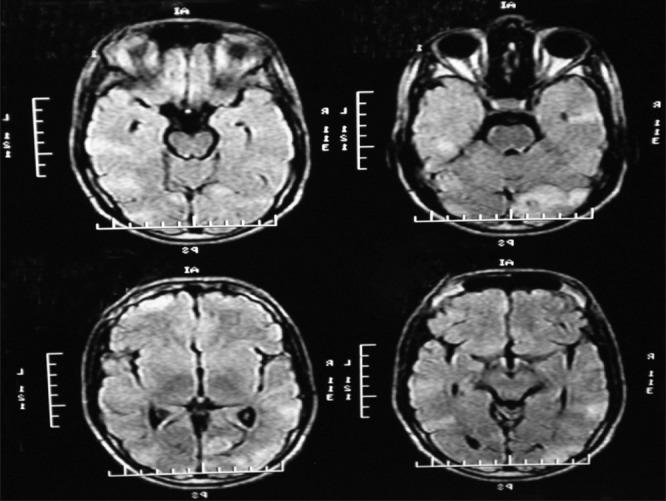

Challenges in the management of a case of tuberous sclerosis.

Tuberous sclerosis complex is a multi-system disorder with autosomal dominant inheritance, which can affect the brain, heart, skin, kidneys, lungs, and retina. We hereby report therapeutic challenges faced in a case of an adolescent male suffering from tuberous sclerosis.